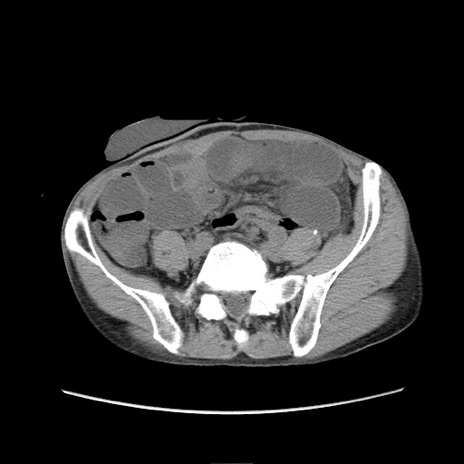

症例11(横断像)

【症例】 60歳代男性

【主訴】 下腹部痛

【現病歴】 本日夜中より下腹部痛の症状認め、受診。

【既往歴】 膀胱癌(膀胱全摘+尿管皮膚瘻術) 、胃癌術後

【身体所見】 BT 35.3℃、PR 58/min、BP 136/98mHg、腹部平坦、軟、腸蠕動音±、ストマ留置あり、左上腹部~正中部に圧痛あり、反跳痛なし。

【データ】WBC 5100、CRP0.01